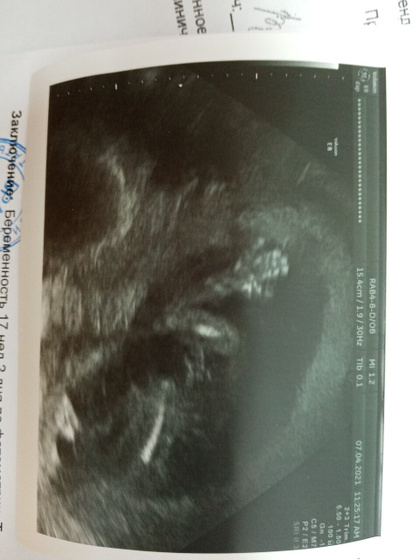

Подтвердили мальчика уже точно ))) дочку конечно тоже хотелось… Ну если получится, значит дочурка впереди ещё будет) теперь можно потихоньку присматривать коляску и т. Д.) ещё и ручкой помахал?

Нам тоже вчера подтвердили мальчика, как и на 1м скрининге, нашего долгожданного!